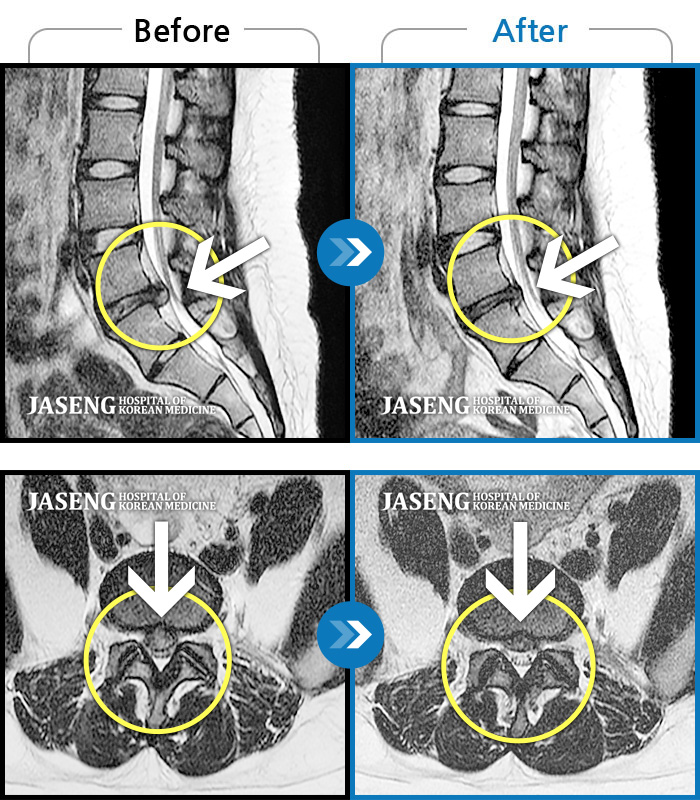

Before

After

환자에게 사전 동의를 받아 동일 조건에서 촬영되었습니다.

개인에 따라 치료 후 부작용이 발생할 수 있으니 의료진과 상담 후 치료를 진행하시기 바랍니다.

허리의 통증과 우측 다리로 방사되는 통증

요추 4번과 요추 5번 사이에서 탈출된 디스크가 신경막을 압박